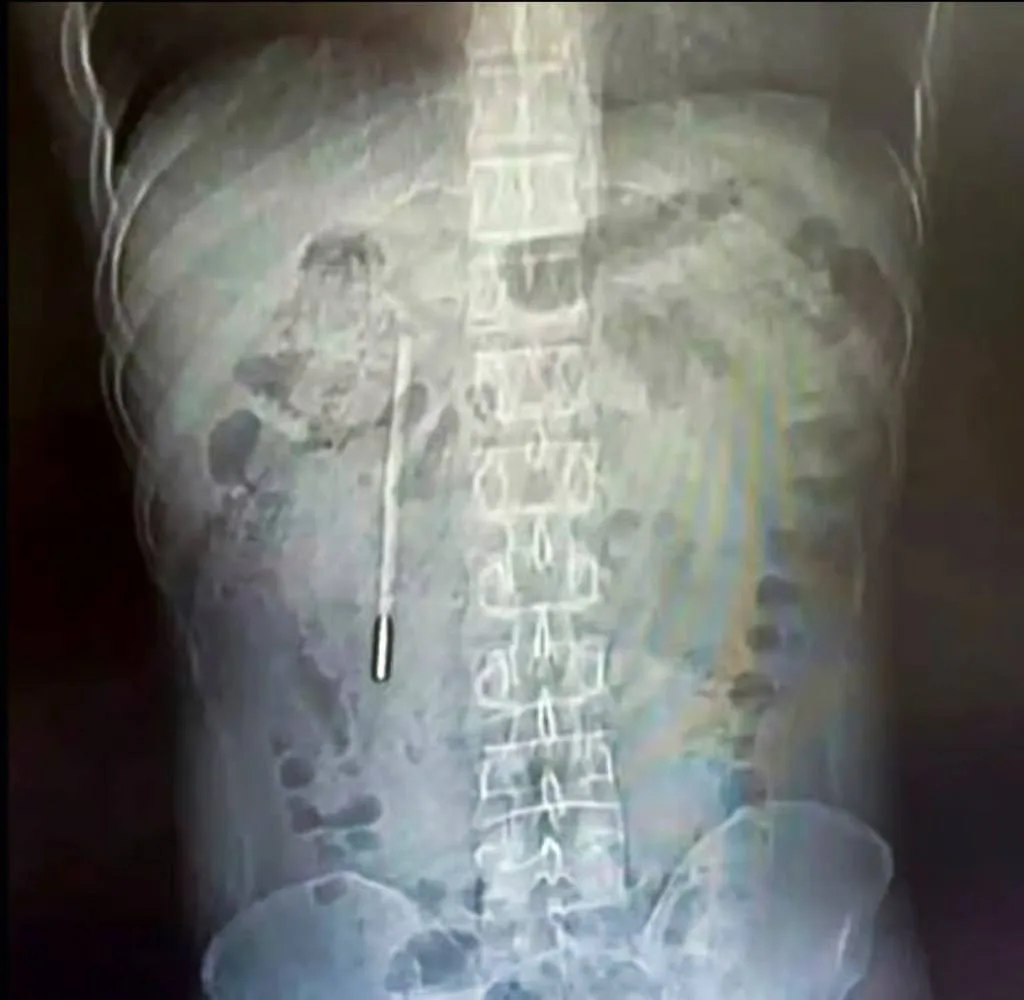

32-летний житель провинции Чжэцзян по фамилии Ван обратился в больницу с жалобами на боли в животе. Обследование показало наличие инородного предмета в двенадцатиперстной кишке — хирурги провели срочную операцию.

Оказалось, что причиной болей был градусник, проглоченный мужчиной в 12 лет. Будучи ребёнком, он побоялся рассказать родителям об инциденте, опасаясь наказания. Со временем Ван и сам забыл о случившемся — предмет не вызывал дискомфорта.

Врачи отметили, что, несмотря на два десятилетия внутри организма, термометр остался целым. Исчезли лишь деления шкалы, поэтому повторное использование изделия невозможно.